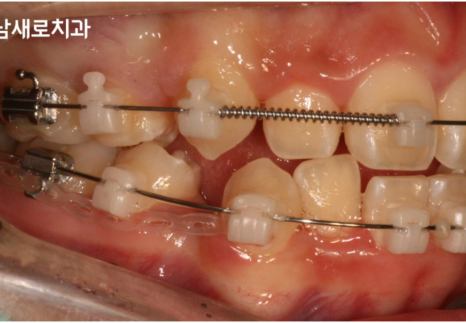

발치교정을 진행하는 과정은

작은 어금니인 소구치를 발치하여

빈 공간을 확보한 후, 앞니를

빈 공간 쪽으로 이동시켜 치열을

올바르게 재배열하는 방식으로

진행되는 치료라고 했는데요.

위 사진을 보시면 왼쪽 사진은

작은 어금니를 발치한 후 촬영한 모습이고,

오른쪽 사진은 소구치를 발치한

빈 공간으로 앞니를 어느 정도 이동시켜

치열을 다시 재배열중인 모습입니다.

작은 어금니보다 안쪽에 위치한

큰 어금니들을 기준으로 앞니가

뒤쪽으로 이동한 모습인데요.

그래서 전과 비교하여도

교합이나 어금니의 위치에

큰 변화가 생기지 않았다는 것을

확인하실 수 있으실겁니다.